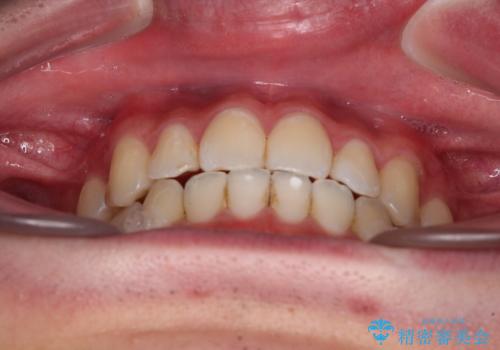

受け口傾向の咬み合わせ インビザラインできれいな口元に

受け口傾向の骨格であり、前歯はクロスバイトまたは切端咬合となっており、叢生は警備であったため、下顎を中心に歯列全体の後方移動を行い、IPR(歯と歯の間を削る)によってデコボコが解消するように設計し、インビザラインにより治療を行うこととしました。

受け口傾向のインビザライン矯正は比較的治療を行いやすいため、きれいに仕上げることができました。舌の突出癖が顕著であったため、改善のためのトレーニングをしっかりと行っていただきました。